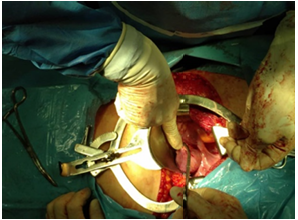

Con relación al tratamiento quirúrgico, se realizó incisión en pared abdominal con una extensión 3 cm por fuera de la tumoración (Figura 3), disección de la lesión, separándola del tejido aponeurótico, percatándose de no dejar implantes de endometriomas visibles en la paciente (Figura 4), se extrajo el total del tumor, donde puede apreciarse el compromiso de piel y del tejido celular subcutáneo (Figura 5). Puede observarse la muestra enviada a estudio anatomopatológico (Figura 6). Se continuó con laparotomía realizando miomectomía, cistectomía de quiste de ovario izquierdo y salpingectomía del mismo lado por apreciar dilatación de esta trompa uterina (Figura 7). Se realizó revisión de cavidad y órganos abdominopélvicos, no apreciando lesiones con características de endometriosis. Se procedió al cierre de la pared abdominal con colocación de malla de Prolene (Figura 8). La paciente evolucionó satisfactoriamente y se retiró la sutura en 7 días (Figura 9).